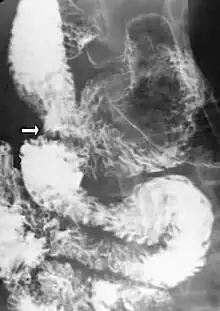

Upper gastrointestinal series showing extreme duodenal dilation (white arrow) abruptly preceding constriction by the SMA.

Diagnosis is can be difficult, and usually one of exclusion. SMA syndrome is generally considered only after people have undergone an extensive evaluation of their gastrointestinal tract including upper endoscopy, and evaluation for various malabsorptive, ulcerative and inflammatory instestinal conditions with a higher diagnostic frequency. Diagnosis may follow X-ray examination revealing duodenal dilation followed by abrupt constriction proximal to the overlying SMA, as well as a delay in transit of four to six hours through the gastroduodenal region. Standard diagnostic exams include abdominal and pelvic computed tomography (CT) scan with oral and IV contrast, upper gastrointestinal series (UGI), and, for equivocal cases, hypotonic duodenography. In addition, vascular imaging studies such as ultrasound and contrast angiography may be used to indicate increased bloodflow velocity through the SMA or a narrowed SMA angle.[13][14]